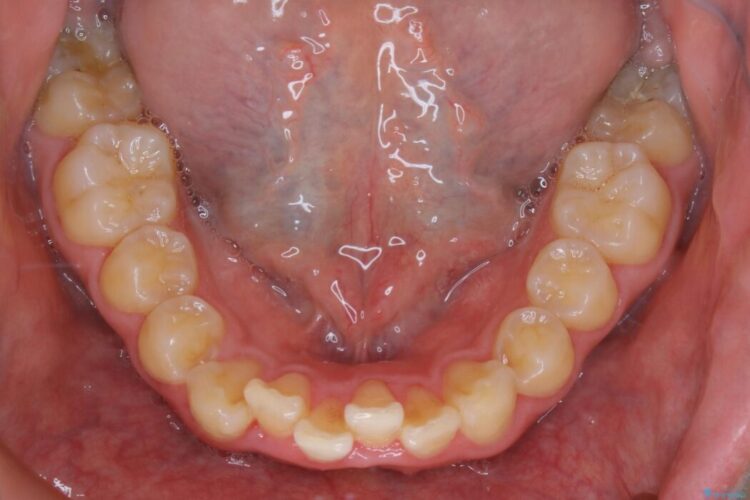

上の歯の出っ歯と下の歯のガタつきが気になるとご来院された患者様です。

出っ歯とガタつきの改善には抜歯が必要と診断し、上下左右第一小臼歯を抜歯することとしました。

抜歯でスペースができるため、歯の移動量が多いことから表側ワイヤー矯正装置で治療を行いました。